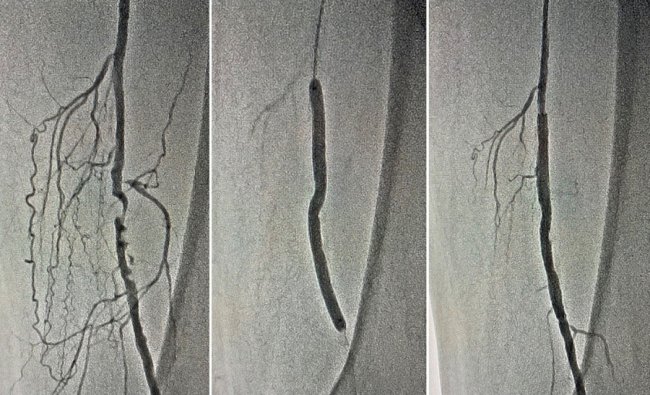

Після проведення ангіографії нижніх кінцівок діагностовано субоклюзію та оклюзію дистальних відділів поверхневих стегнових артерій - 100% і 98%. Команда ендоваскулярних хірургів провела стентування обох артерій через проколи в паху.

Операція пройшла успішно. Лікарям вдалося повністю відновити кровотік в судинах та запобігти втраті обох кінцівок. Нині біль в ногах пацієнта не турбує. На третій день після операції його виписали з лікарні.